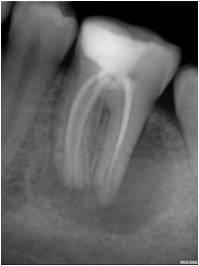

Fotos de casos clínicos